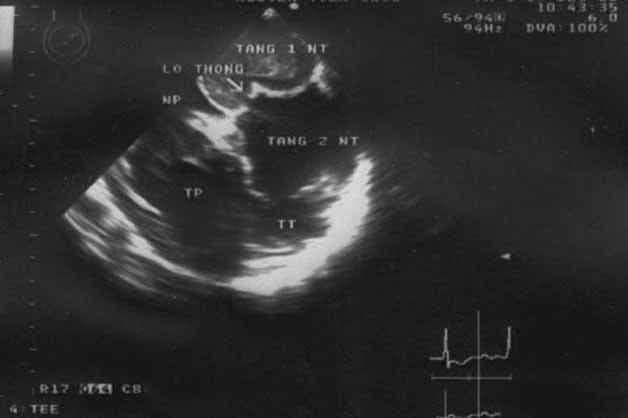

Hình ảnh siêu âm tim qua thực quản

Phương pháp siêu âm tim qua thực quản có thể cho hình ảnh rõ ràng hơn của các van tim, tâm nhĩ so với siêu âm tim thông thường. Từ đó sẽ giúp các bác sĩ có thể tìm ra những vấn đề trong chức năng và cấu trúc của tim. Ngoài ra, nếu người bệnh có thành ngực dày, có băng vùng ngực, bị béo phì hoặc đang sử dụng máy thở thì phương pháp này sẽ giúp bác sĩ dễ dàng quan sát hơn.

Siêu âm tim, hay còn gọi là transesophageal echocardiogram (TEE) test, là phương pháp sử dụng sóng siêu âm để tạo ra các hình ảnh chuyển động trong tim và các mạch máu chính. Siêu âm tim sẽ giúp bác sĩ phát hiện ra một số bệnh lý về van tim, bệnh cơ tim, khối u, viêm nội tâm mạc nhiễm trùng, bệnh màng ngoài tim,… Ngoài ra còn giúp phát hiện một số bất thường bẩm sinh tim và phình giãn động mạch chủ ngực.